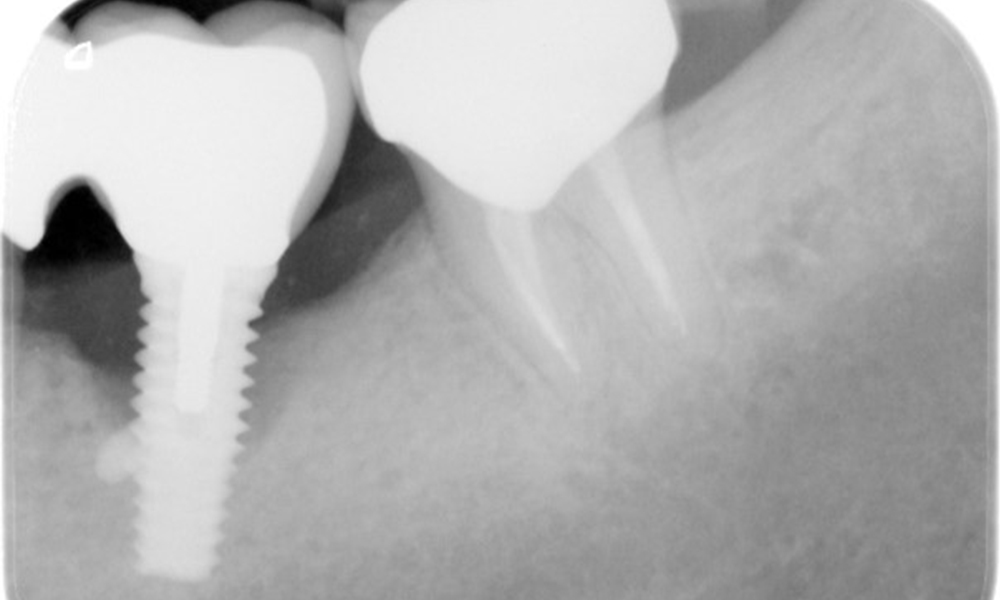

The X-ray images show the progression of bone loss in the area of the implant in region 36: dental film from 11.02.2021 (left) and dental film from 18.01.2024 (right).

OPG: 26/02/2024 Dental X-ray: 18/01/2024

The patient has no particular risk factors with specific dental implications in his medical history. The key factor, therefore, is the requirement in terms of oral health. In this respect, there is evidence of a probing depth of 5 mm at the implant in the 3rd quadrant and, on the X-ray image, increased bone loss. The patient also has currently stable early periodontal disease and two active initial carious lesions.